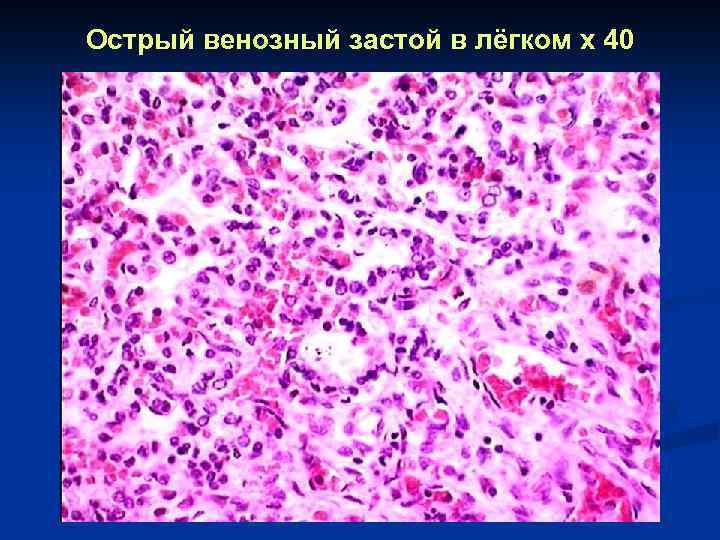

Острый венозный застой в лёгком x 40

Острый венозный застой в лёгком x 40

Острый венозный застой в лёгком x 40